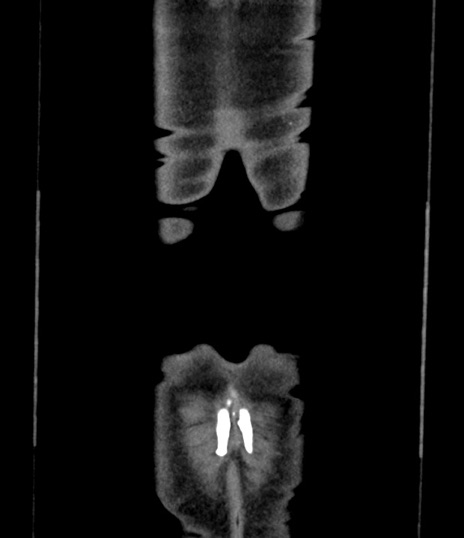

横断像